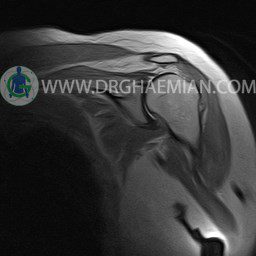

ام آر آی آتروفی عضلانی کتف بیمار

ام ار آی کتف یک روش تصویربرداری است که به وسیله آهنرباهای قدرتمند از قسمت کتف تصاویری ایجاد می کند. این نوع تصویربرداری از تشعشعات استفاده نمی کند. در این کیس آتروفی عضلانی کتف به همراه پارگی تاندون بالاخاری، بورسیت ساب دلتوئید و افیوژن مفصل دیده می شود.

LEFT SHOULDER MRI

(Without contrast)

Technique: Axial T1 and GE , coronal T1 , T2 , sagittal T1 , T2 .

REPORT:

The humeral head has normal configuration and articulates properly and parallelism with the normally developed glenoid .

The articular surfaces are smooth and show normal cortical thickness .

The bone marrow displays homogeneous , fat – equivalent signal intensity .

The glenoid labrum is intact on all sides .

The biceps tendon appears normal and occupies a normal position in the bicipital groove.

The other muscles that cover the shoulder joint appear normal , as do imaged portions of the lungs and soft tissues .

– Complete tearing of supraspinatus tendon with grade 2 retraction and muscle atrophy

– AC joint hypertrophy with subacromial – subdeltoid bursitis

– Glenohumeral joint effusion

are seen.